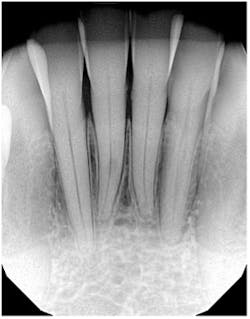

I almost missed this lesion on the radiograph

The distinct radiolucency on no. 25, just below the lower apical half of the tooth, is external resorption. The key diagnostic feature that differentiates it from internal resorption is the fact that the canal is defined. The CBCT confirms this, of course.